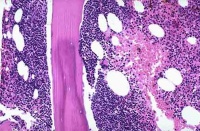

恶性淋巴瘤在病理学上分成何杰金氏病和非何杰金氏病两大类,根据瘤细胞大小、形态和分布方式可进一步分成不同类型。

(一)何杰金氏病(HD) HD是一种特殊类型的恶性淋巴瘤,组织学诊断主要依靠在多形性炎症浸润背景上找到特征性R-S细胞。1965年,Rye国际会议确定分为四型:

1.淋巴细胞为主型(LP)HD2以中、小淋巴细胞增生为主,有时以组织细胞增生为主;典型R-S细胞不易找到。但常存在较多L-H细胞。

2.结节硬化型(NS)HD:以双折光宽胶原纤维束,将存在腔隙型R-S细胞的淋巴组织分隔成大小不一结节为特征,典型R-S细胞罕见。

3.混合细胞型(MC)HD:典型R-S细胞和H细胞多,炎性细胞明显多形性,伴血管增生纤维化

4.淋巴细胞消减型(LD)HD:除存在典型R-S细胞外,还可出现许多多形性R-S细胞(网状细胞型)或弥漫性非双折光纤维组织增生,反应性炎性细胞显著减少。